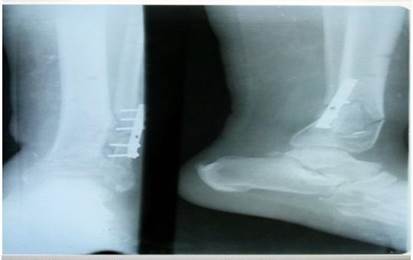

Como parte del plan quirúrgico trazado se realizó la limpieza quirúrgica requerida y se optó por la colocación de un fijador externo monopolar en puente para controlar la fractura del pilón, al montaje referido se le asoció una placa semitubular de un tercio de caña de seis perforaciones para estabilizar la lesión peroneal. (Figuras 4, 5, 6, 7).

La consolidación de la fractura se obtuvo a las 12 semanas, el fijador externo se mantuvo todo este tiempo y afortunadamente los resultados finales fueron considerados satisfactorios tras la culminación del periodo de fisioterapia. (Figura 8).